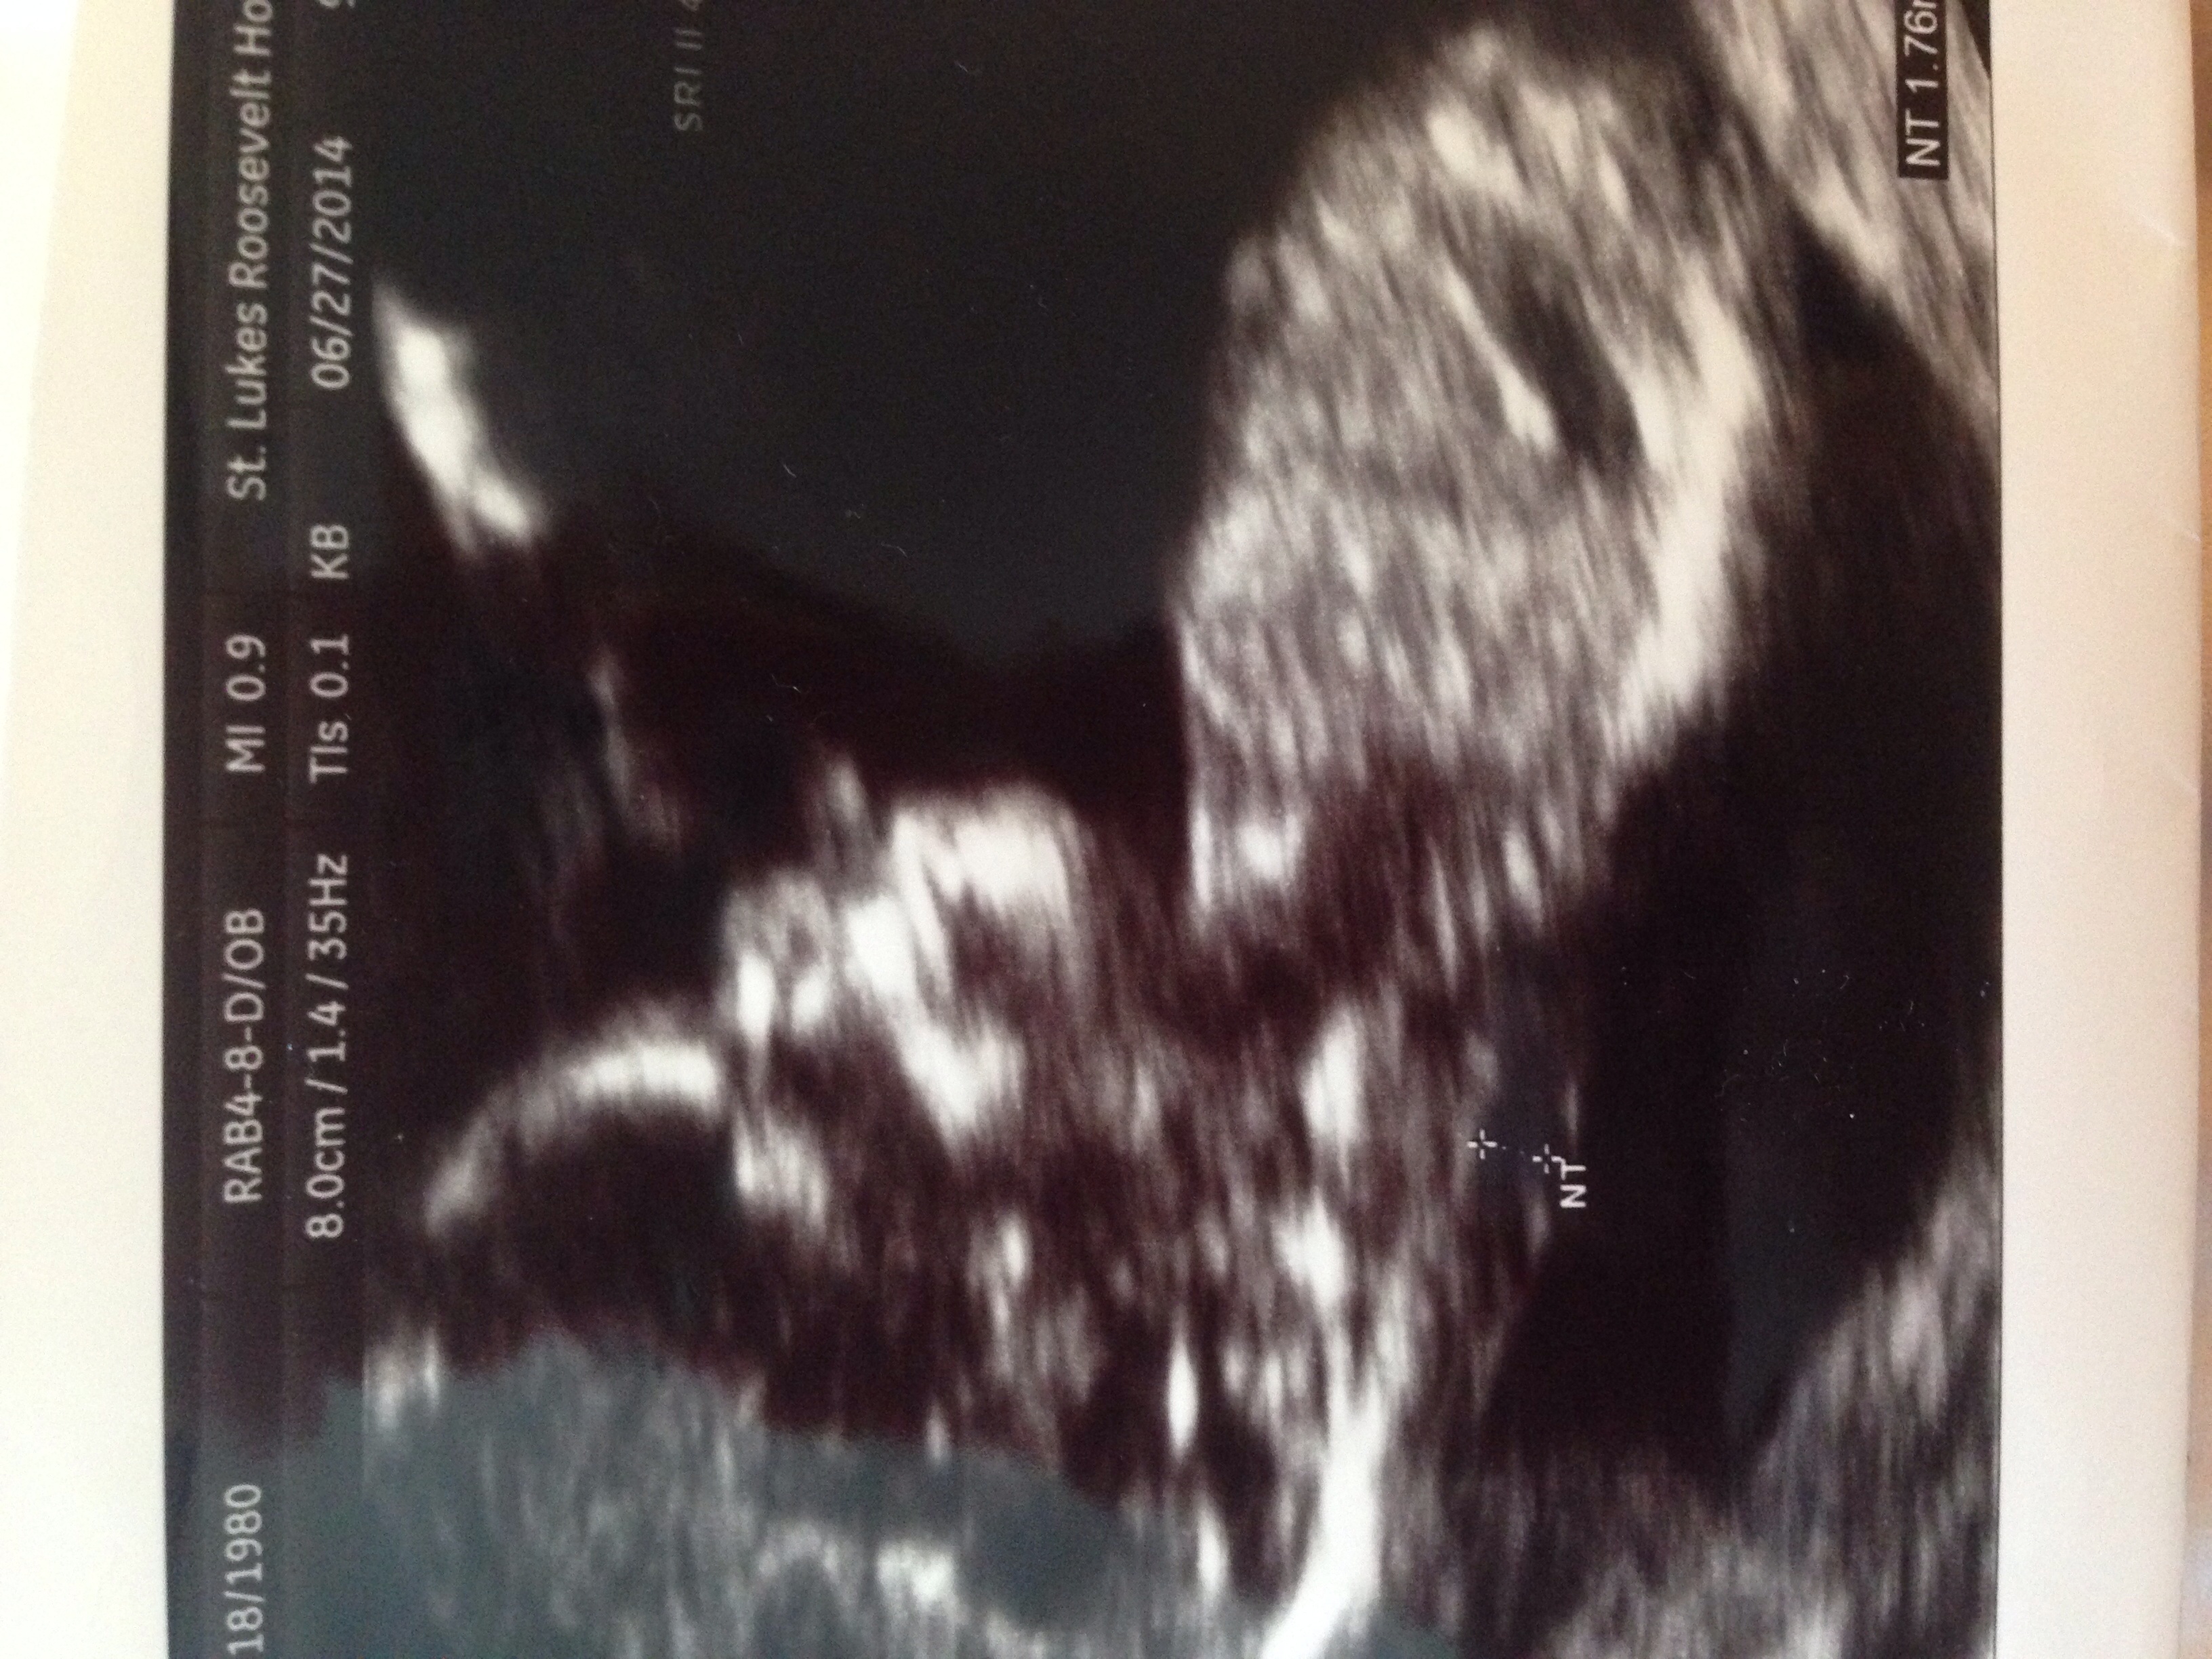

Although about a month ago we got word that the NT results looked good, they drew blood last Monday as a last step to the test and my doctor called today to say that the results of this last blood test were "slightly abnormal." Now I have to probably go through more tests for Down Syndrome. We made an appointment with the genetic counselor at the hospital for tomorrow afternoon so I'll learn more about our options at that point. The doctor said not to freak out since there are false positives with the NT scan, but I cant help it - I'm freaking out. I cant handle this emotional roller coaster.

I had a similar situation with my first pregnancy. I was so upset. After doing some research I found out that an increased risk result is kind of common and most of the time that baby is perfectly fine. Its completely normal to be sad and to worry but remember that you don't have definite results yet. Try to relax until you get the results back. Praying that your baby is perfectly healthy! Also, look at your ultrasound pictures from when they did the scan. Do you see evidence of a nasal bone? A lot of DS babies don't have a visible nasal bone at that scan so if you see one its another sign that everything is okay. I wasn't sure what it was supposed to look like so I Googled it and sure enough my little girl had a visible one which made me feel a little better!!

• I didn't know this about the nasal bone. There is definitely a visible nasal bone in the scan. That made me feel a lot better.

I feel for you; it is such a nerve wracking experience. We went through the same thing (nuchal translucency of 3.2 mm at the NT scan). We met with the genetic counselor that day and she sent us for a Verifi blood test (similar to Panorama and the other cell-free DNA tests). Thankfully, everything came back normal. The results took five business days and it was one of the longest weeks of my life.

• You are all so sweet. We met with the genetic counselor yesterday - right now the risk from the last round of blood test said the baby has a 1 in 70 chance of having Downs. We did the math - that's a 1.4% chance.

We opted for the cell free DNA blood test as a next step and they took the blood yesterday. I'll know in a week. Now we wait.